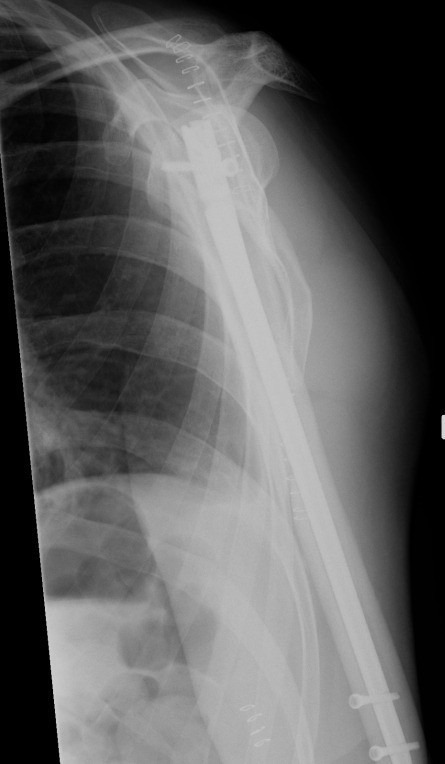

Prox humerus 1Prox humerus 2Prox humerus ORIFProximal humerus ORIF

Proximal third humerus ORIF of nonunion